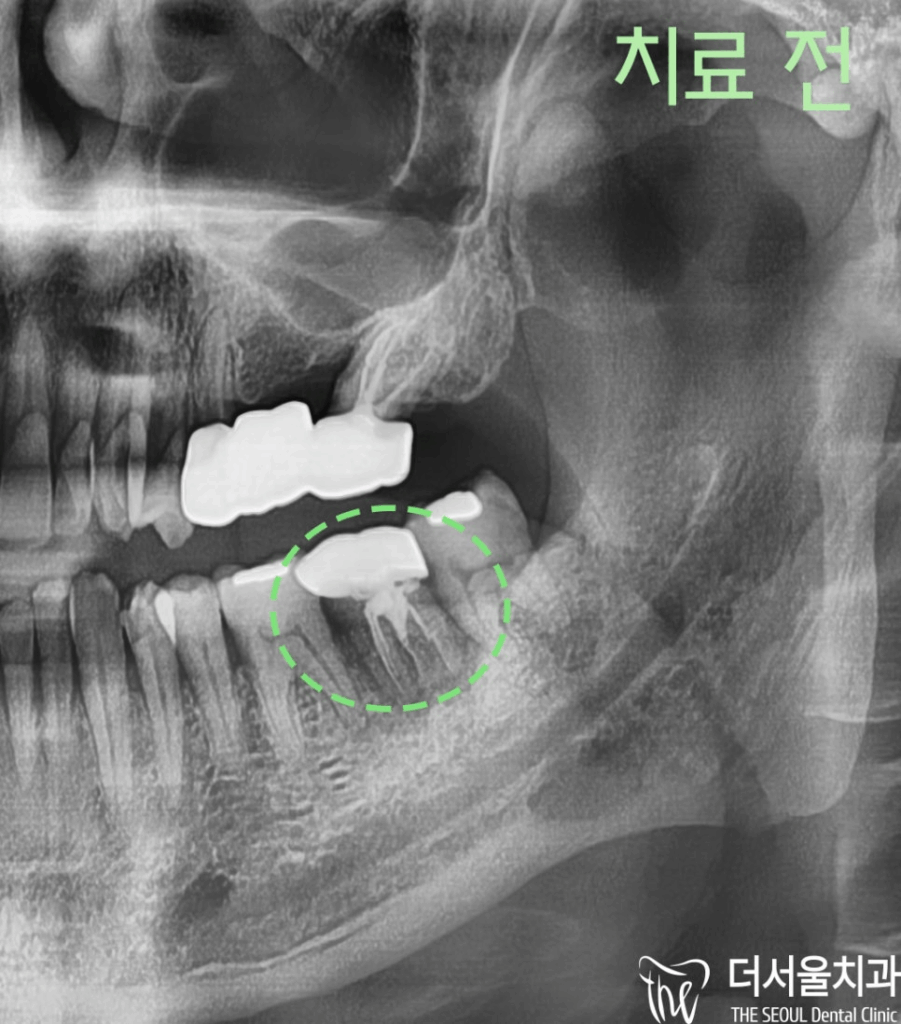

수술 전

파노라마 사진을 보여드리면

#37번 치아 주변이 어두운 것을 확인할 수 있습니다.

이것이 의미하는 바는

치아를 감싸고 있는 치조골이 녹아내려서

파노라마 상에서 음영으로 나타난 것이었습니다.